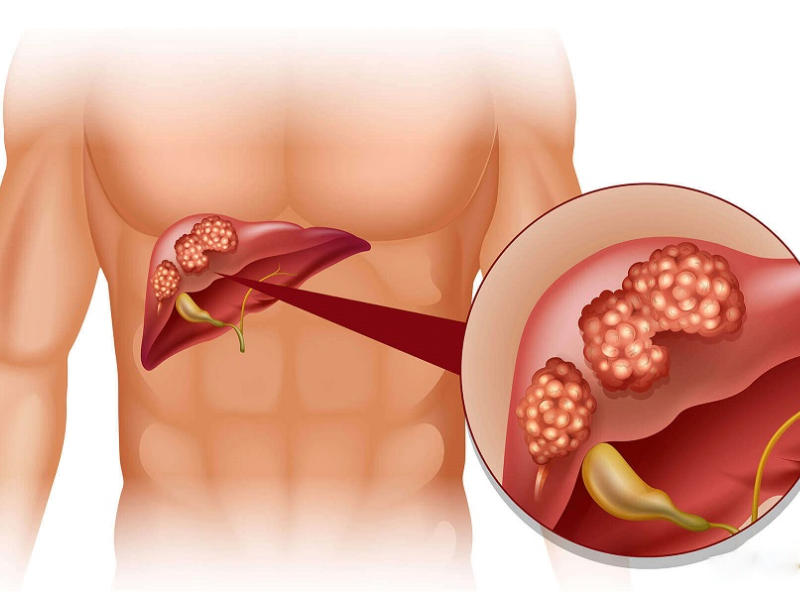

سرطان کبد یکی از بیماریهای جدی و نسبتا شایع دستگاه گوارش است که سالانه جان هزاران...

- ۲۳ جولای ۲۰۲۵